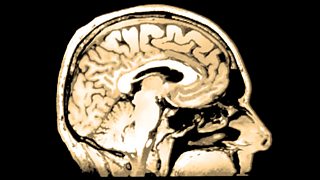

Photos from the life of Henry Molaison.